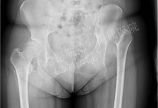

【髋关节】保髋手术复杂病例介绍(一)

病情概述:   患者,女性,23岁,左下肢跛行20余年。  骨盆X线片显示:左髋关节高位脱位。  下肢全长片显示:左下肢相对短缩。  髋造影MR片显示:左股骨头软骨质量欠佳。 [详情]